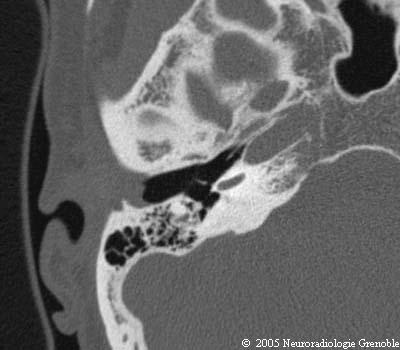

Radioanatomie TDM du rocher normal

Conduit auditif externe

Tympan

Marteau (manche)

Cochlée

Canal carotidien